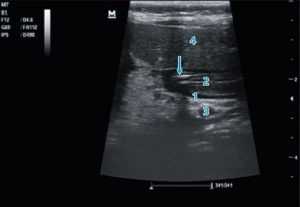

Рис. 3. Продвижение питательного зонда по пилорическому каналу: 1 — тело поджелудочной железы; 2 — пилорический канал; 3 — селезеночная вена; 4 — паренхима печени. Проекция зонда указана стрелкой — виден двойной параллельный контур

Fig. 3. Advancement of the nutrient tube along the pyloric canal 1 — body of the pancreas; 2 — pyloric canal; 3 — splenic vein; 4 — parenchyma of the liver. The projection of the probe is indicated by an arrow — a double parallel contour is visible